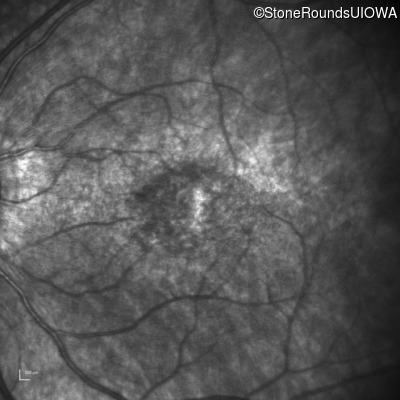

Age at visit: 17 years

This 17 year old female feels that the vision in her right eye has worsened since her cataract surgery 8 weeks ago.

SECORD CRB1 Cys195Phe TGC>TTC Gly750Asp GGC>GAC AR